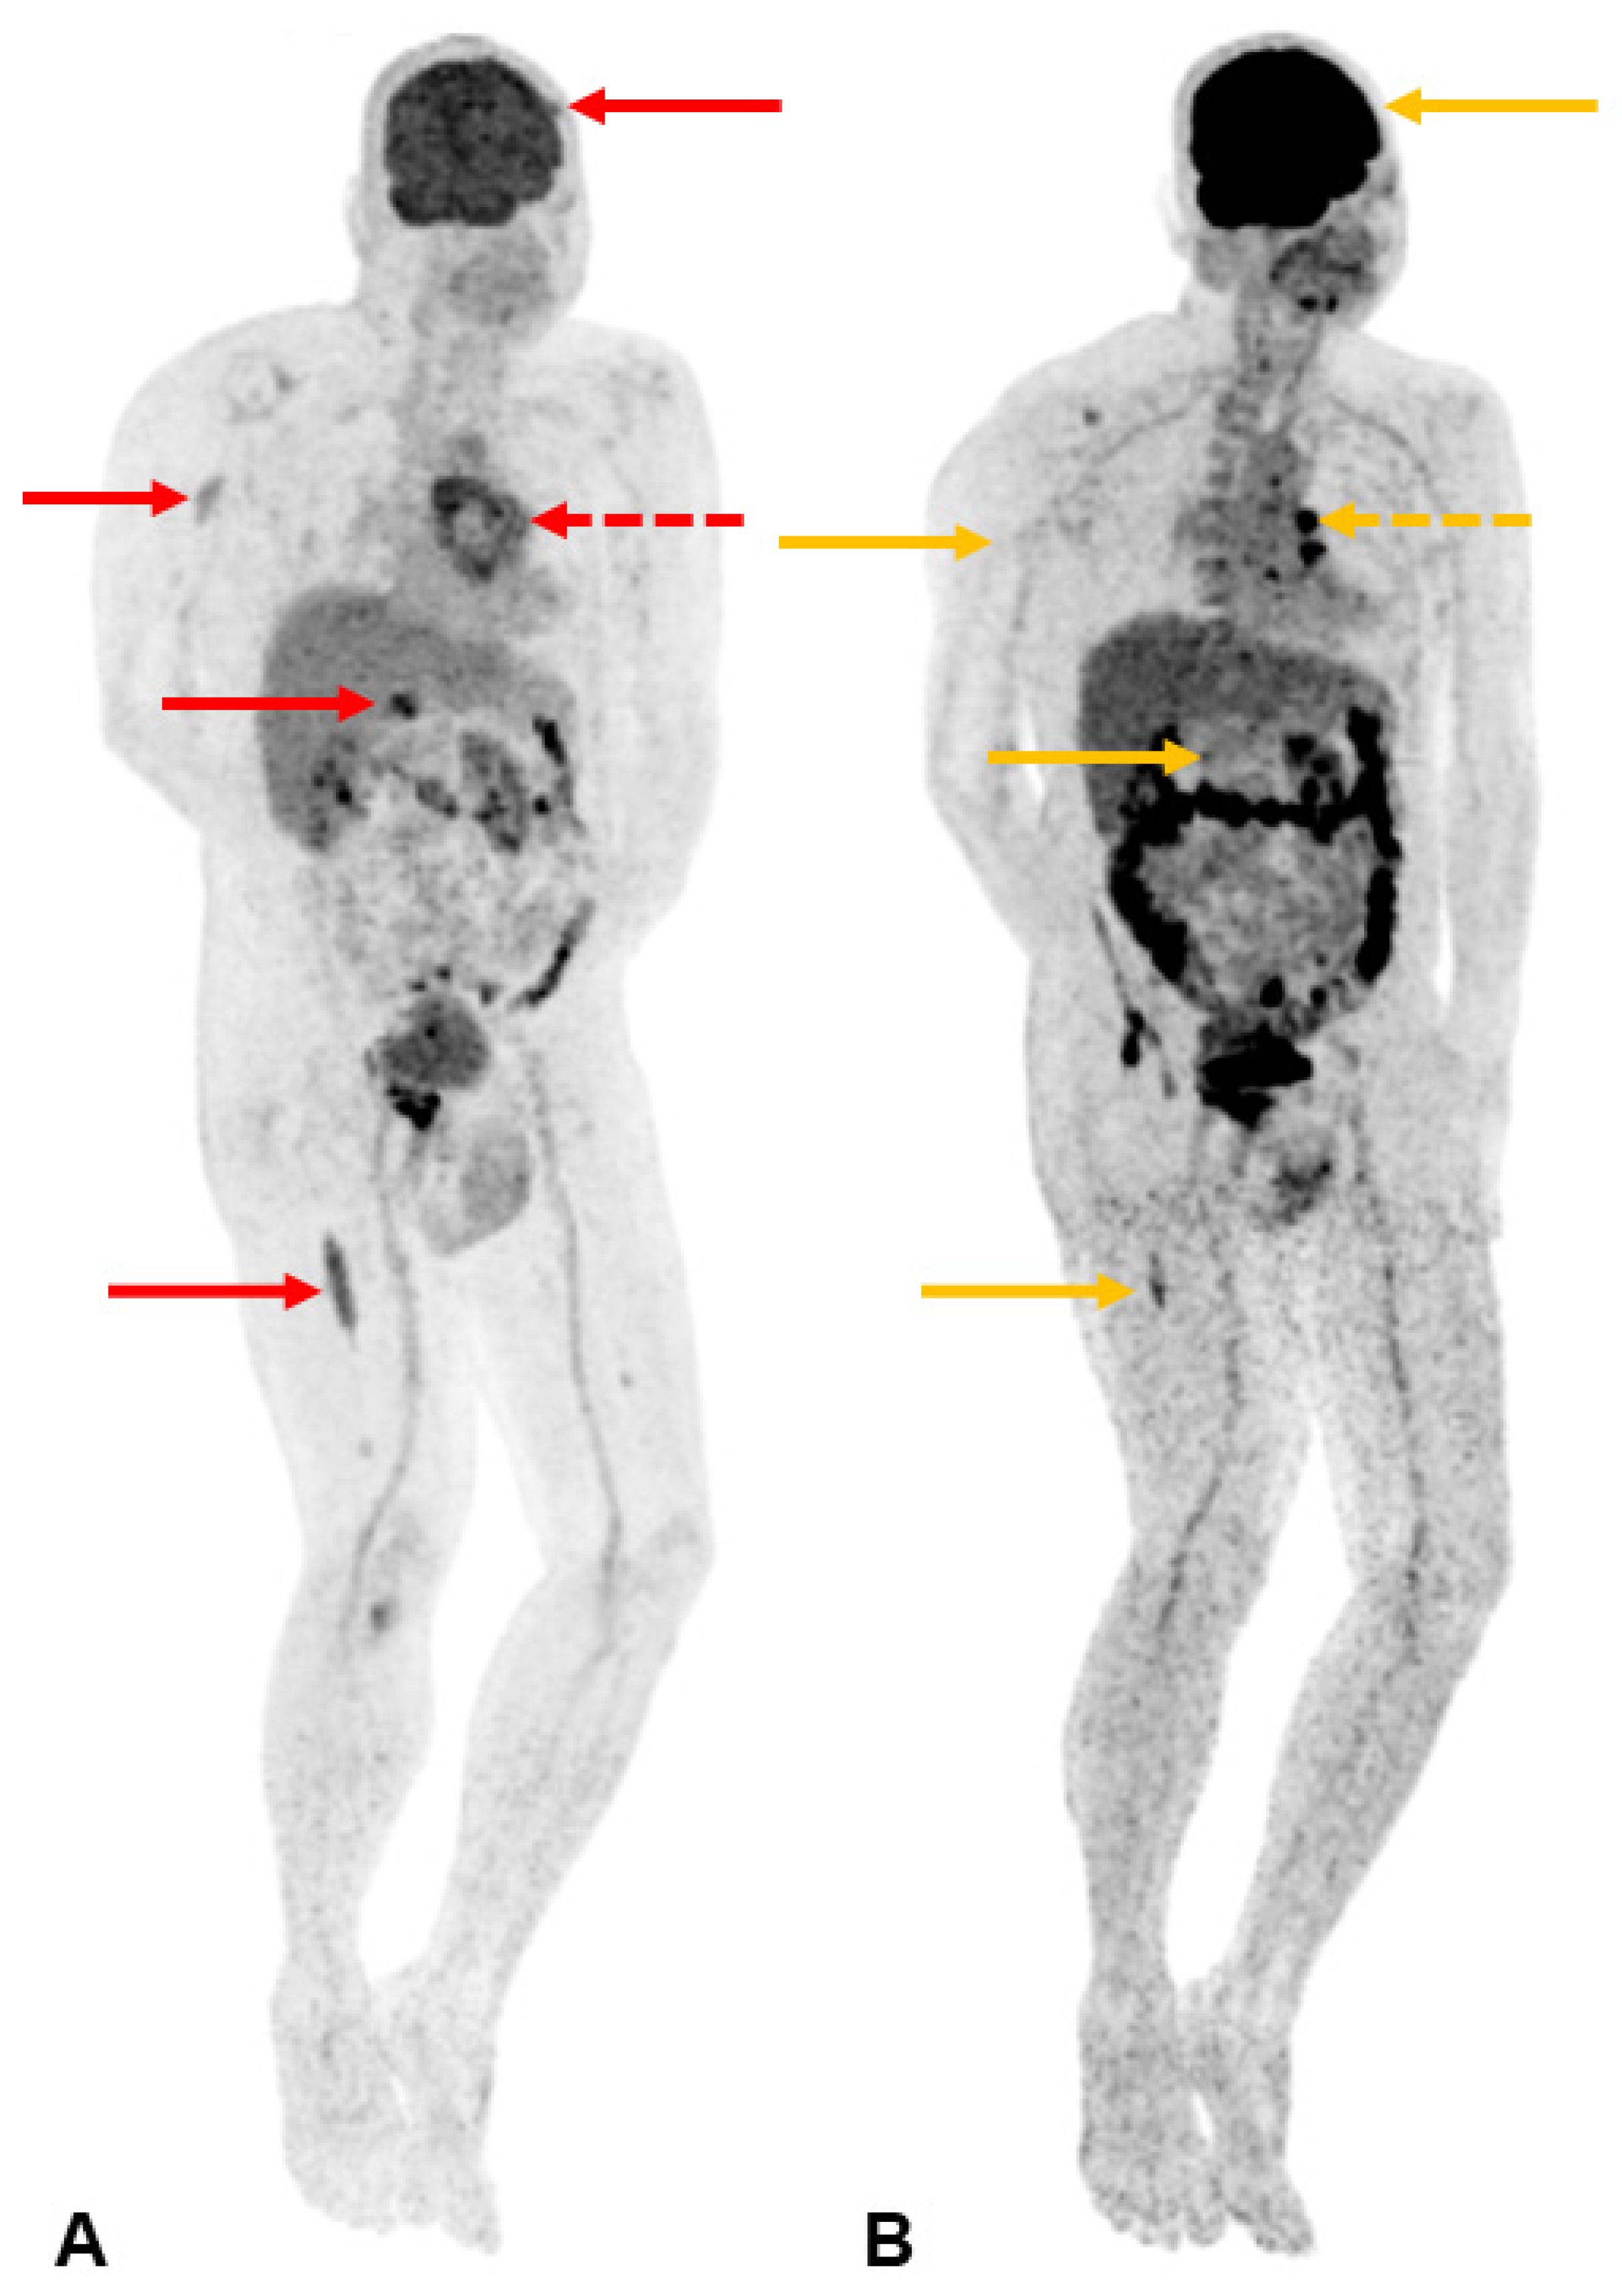

Magnetic resonance imaging (MRI) of the anterior chest wall with selected axial fat-suppressed short-tau inversion recovery (STIR, (A)) and sagittal T1-weighted (B) images. A fairly homogeneous 8.7 cm mass is seen encasing a sternal wire, appearing as focal susceptibility (yellow arrow). The sagittal image shows diffuse marrow infiltration in the deformed and expanded sternal body (white asterisk) with a large extra-osseous mass extending into the anterior soft tissues (yellow asterisk) through a relatively preserved cortex (linear hypointense signal indicated by the dotted white arrow). While this appearance has been described in osseous lymphoma [2], it can also occur in other malignant round cell lesions of bone, including plasma cell neoplasms [3]. This is likely due to permeative tumour growth via cortical neurovascular channels, allowing relative cortical preservation despite the large extra-osseous component. Other differentials for this MRI appearance include Ewing sarcoma or primitive neuroectodermal tumour (PNET), but these occur predominantly in the paediatric population. Histological evaluation of the lesion revealed a plasma-cell-rich lesion with occasional plasma cells demonstrating nuclear atypia and plasmablastic-type morphology. The plasma cells also show evidence of kappa immunoglobulin light chain restriction using in situ hybridization techniques. Bone marrow biopsy demonstrated an infiltrate of neoplastic plasma cells within the intertrabecular spaces, comprising 60% of the nucleated cell population. Further laboratory investigations revealed elevated total serum protein levels of 105 g/L (normal range 65–82 g/L), with a kappa free light chain (FLC) level of 256.7 mg/L (normal range 3.3–19.4 mg/L) and free kappa-lambda ratio of 42.08 (normal range 0.26–1.65). The IgG level was 53.2 g/L (normal range 5.0–15.0 g/L) and B2-microglobulin level was 5.59 mg/L (normal range 0–1.9 mg/L). Cutaneous plasmacytomas have been known to develop at sites of previous surgery or trauma, whether as a secondary lesion in patients with known plasma cell disorders [4,5] or as a primary lesion [6,7]. However, we believe that this is the first description of a primary plasma cell disorder presenting with both osseous and extramedullary disease at the site of previous sternotomy. The predilection of plasma cell neoplasms for sites of injury or scar formation is not well understood. It has been postulated that the inflammatory mediators present in scar tissue to facilitate wound healing (such as interleukin-6, interleukin-8, and tumour growth factor-β) can result in the selection of a clonal plasma cell population and also support tumour growth and survival [5,7].